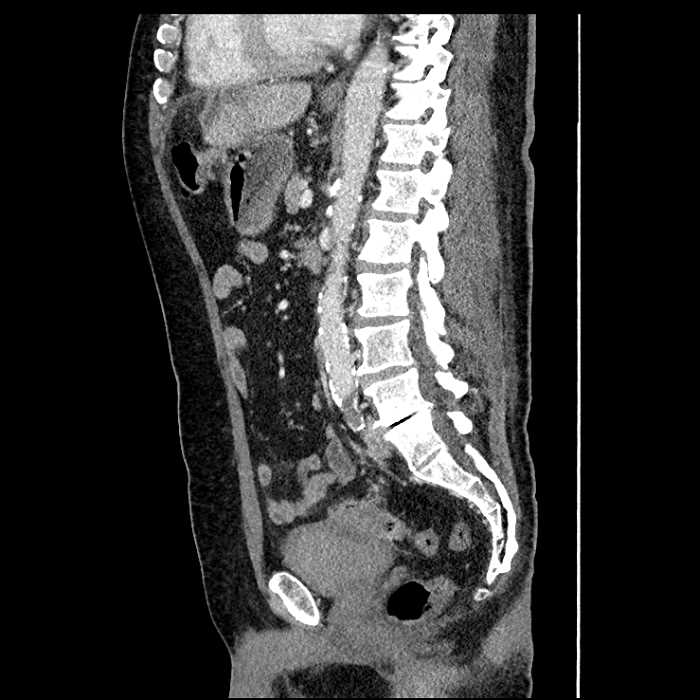

• High grade stenosis of the left common iliac artery, with the left internal and external iliac arteries remaining patent

• Ankylosis of both sacroiliac joints

High grade stenosis of the left common iliac artery. The left external and internal iliac arteries are patent.

Hepatic abscess showing the double target sign with low density internally surrounded by a thin inner enhancing rim (red arrow) and ill-defined outer low density rim (yellow arrow). Blue arrow indicates an internal septation. Red arrows: additional smaller subcapsular abscesses. Red arrow: focal contained perforation associated with diverticulitis.